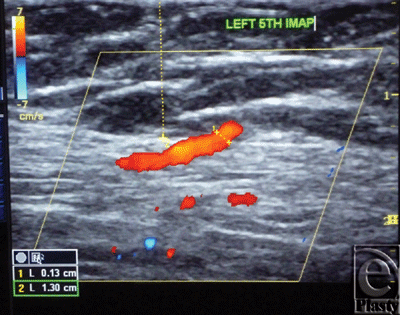

The site of the detectable perforator(s) was projected by a colored marker on the patient's skin so as to estimate the label remoteness (representing the perforation site) from the sternum (Fig 2), and the number of encountered perforators parasternally in each investigated space was counted as well. The inner diameter of each perforator was measured (Fig 3). Figures 4 to 8 show color duplex photos for perforators penetrating the fascia to reach the dermoglandular target.

| Figure 3. Color Duplex photo shows the diameter and depth of a certain visualized 5th internal mammary artery perforator from the skin surface. The point of measurement was at the perforation point. |

![]() |

| Figure 4. Color Duplex photo shows a 4th internal mammary artery perforator while perforating the superior surface of the pectoralis major muscle (the dashed line). |